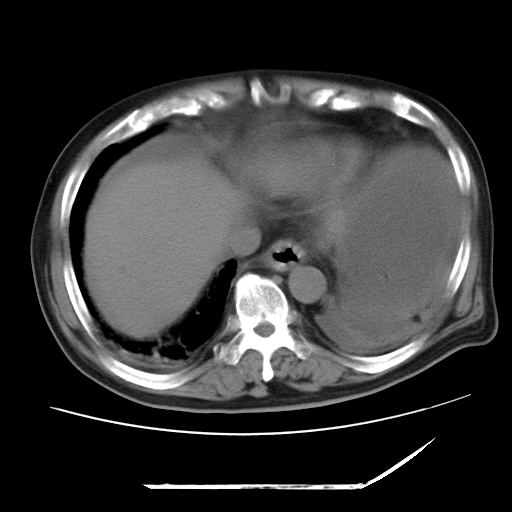

以下是引用zxl51642在2009-8-12 18:55:00的发言:[br]1、肠系膜脂肪浑浊,密度增高,腹水,支持腹膜炎诊断;2、右肾盂及输尿管中段结石,左输尿管起始段结石;3、胆囊切除术后改变?4、双侧胸膜腔少量积液;5、胰腺体积不大,勾勒清楚,肾前筋膜无增厚,不支持胰腺炎,请结合血尿淀粉酶及临床。